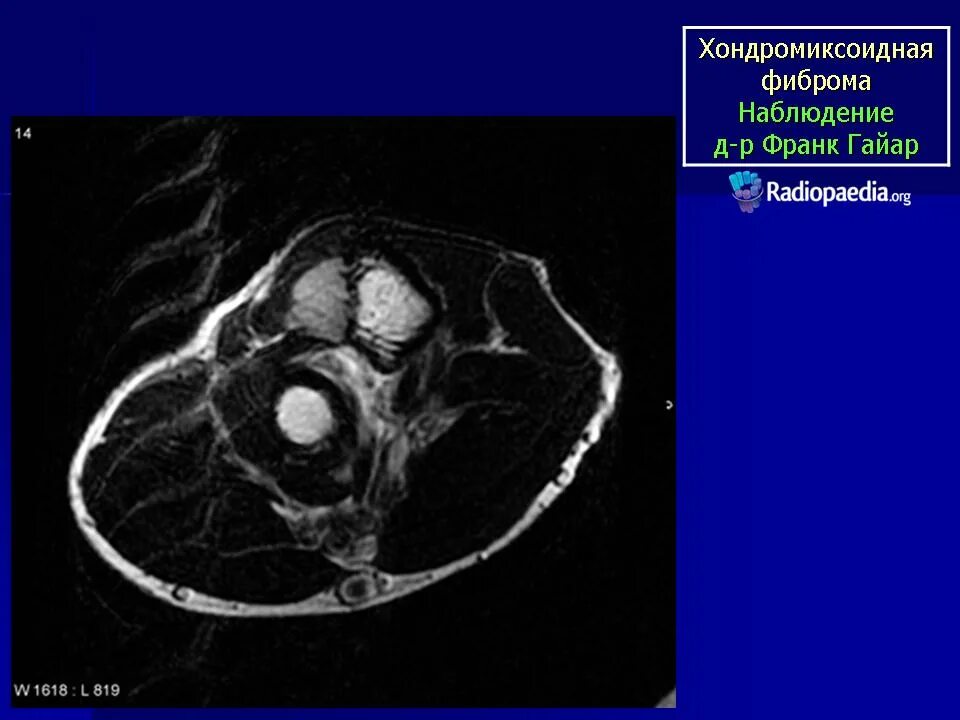

Фиброма кт